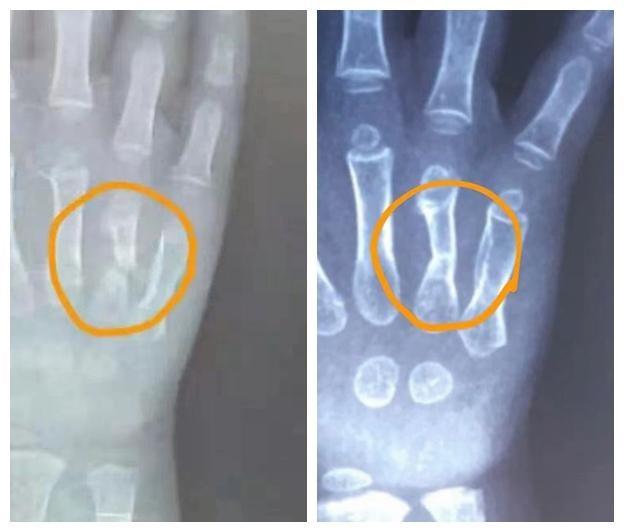

脊柱外科:颈椎病,腰椎间盘突出症,腰椎管狭窄症,肌筋膜炎,棘上韧带炎,腰椎术后综合征等引起的慢性颈肩腰腿疼痛的保守治疗。 矫形骨科:早期骨性关节炎和股骨头缺血性坏死,髋关节及膝关节慢性损伤性疾病,如弹响髋,跳跃膝;足跟部疾病,如跟痛症、跟腱炎等。 运动损伤科:肩部慢性损伤性疾病,如冻结肩、撞击综合征、肱二头肌长头肌腱炎、钙化性冈上肌腱炎等;肘部慢性损伤性疾病,如肱骨外上髁炎,肱骨内上髁炎;髋关节痛,踝关节痛,膝关节痛。 创伤骨科和小儿骨科:骨折延迟愈合或不愈合。 手外科:骨折延迟愈合或不愈合,网球肘,腱鞘炎等。 足踝外科:足跟部疾病,如跟痛症、跟腱炎,踝关节痛等。 风湿免疫科:强直性脊柱炎。 胸外科:肋软骨炎。